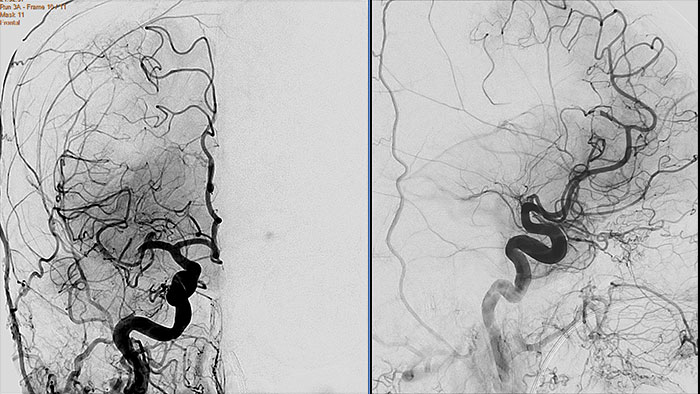

Contrast arterial structures with surrounding bone and soft tissue to assist in identification of vascular abnormalities

The XA Vascular Processing – DSA (in MMV) expands your workflow by allowing you to read and post-process iXR images virtually anywhere. Obtain images of arteries in various parts of the body using tools to perform standard and run subtractions, pixel shifting, and landmarking. This application also provides post-processing tools to edit and optimize the DSA XA data created in the interventional room.

Benefits